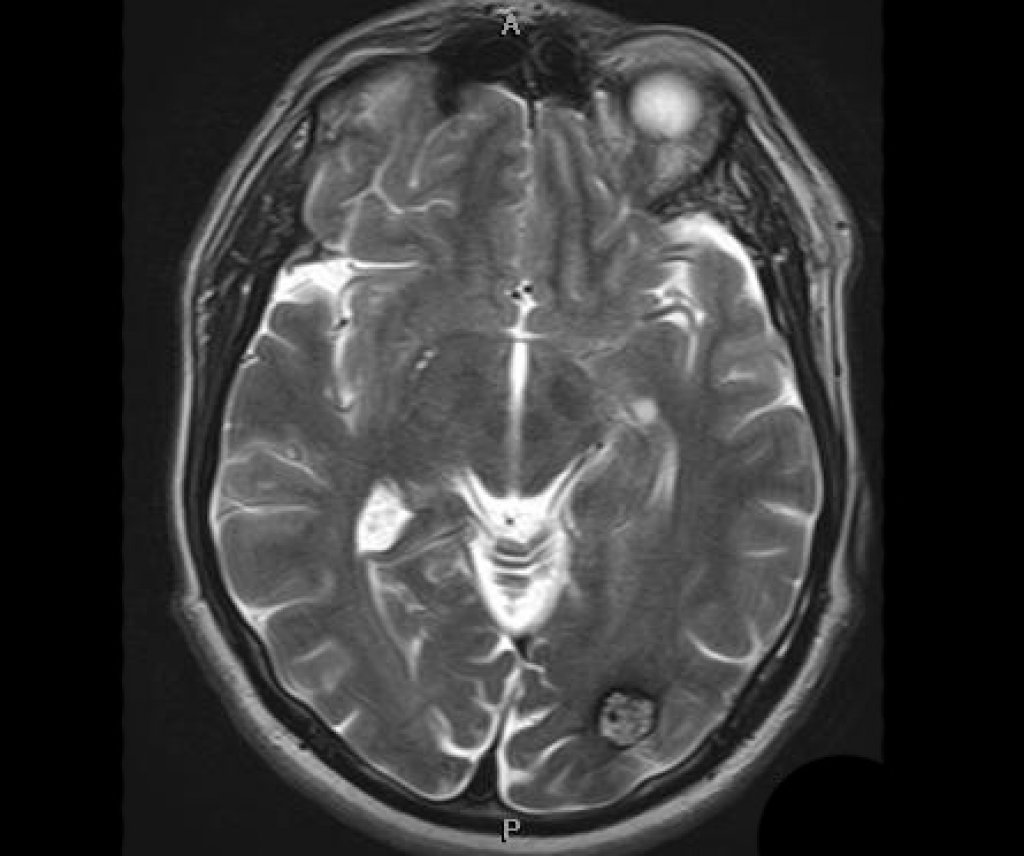

- Комплексная диагностика. Проводятся высокоточные исследования: магнитно-резонансная томография (МРТ) с контрастированием, компьютерная томография (КТ), ангиография сосудов головного мозга. Эти методы позволяют хирургу увидеть точное расположение, размер и структуру образования, а также его взаимоотношение с сосудами и функциональными зонами мозга.

- Долгосрочная реабилитация. После выписки начинается самый важный этап. Он может включать занятия с физиотерапевтом для восстановления двигательных функций, с логопедом для коррекции речевых нарушений и с нейропсихологом для улучшения памяти, внимания и мышления. Важно строго следовать рекомендациям врача, принимать назначенные препараты и регулярно проходить контрольные обследования (МРТ, КТ).

- Долгосрочное наблюдение. После операции необходимо регулярно проходить контрольные осмотры у нейрохирурга и делать МРТ или КТ головного мозга, чтобы отслеживать процесс восстановления и вовремя выявлять возможные рецидивы заболевания.